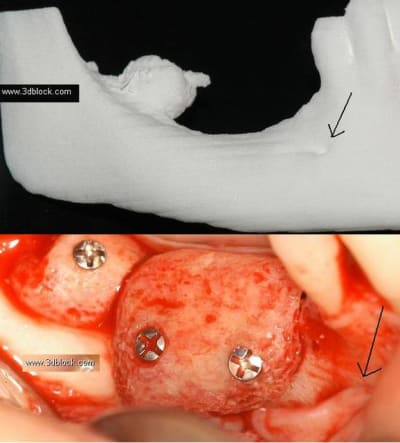

Patiente agée d'une trentaine d'année. En bouche la crête osseuse est inapparente et absence de gencive attachée.

Dans les secteur d'emmergence du nerf mandibulaire la palpation est douloureuse.

Effectivement, dans la mesure ou on ne doit gagner qu'en largeur, je ferais une régénération en utilisant des vis en tuteur et du puros.

1. 2 séances d ostéotension

2. Epaississement vestibulaire en zone molaire nanobone prfd jason

3. pose de 2 cylindres enfouis en 34 44

4. pose de monodisk en 36 37 46 47 enfouis bloqués par vis ostéosynthèse

Pour le gain en hauteur, il n'y a que la greffe autogène qui donne de bon résultats, avec des bloc allogenique ???

Bien vu! Je ne connaissais pas. C'est le même cas. J'aurai bien tenté mais ce qui "m'inquiète", c'est l'emmergence du mandibulaire. Sur le modèle du site je ne le vois pas; sur mon cas il serait juste au niveau du premier bloc et je me pose la question du surplomb ou de "l'irritation" possible.

Pour le cas 3Dblock, c'est fait avec des blocs Puros, donc pas de prélévement. Les blocs sont pré-taillé sur un modéle issu du scan. Le modèle est fait en italie, et est stérilisable. on stérile le modéle, un champ, et un paire de gant stérille, et on façonne le block. Ensuite, il faut le stocker pour l'intervention. il n'est pas re-stérilisé.

On vois le mentonnier, mais je ne sais pas pour ton cas. pour avoir une bonne laxité du lambeau, il est necessaire de dissequer le mentonnier sur 8-10 mm, ( jamais fait, mais j'ai vu faire... )

Nous avons traité un cas comme ça avec D57,(secteur 3) os D1, manque de largeur résultat (de mémoire je n'ai pas les photos ici) 2 implants en même temps que l'expansion (34/37) et la suite 3 mois après le déplacement des volets vestibulaires, (bloqués sans vis) mais protégés par un bridge provisoire.

En conclusion, ce n'est pas un cas ou je ferais une greffe même pré ajustée (résultats en Décembre Pluton), mais une expansion sans doute avec déplacement/fracture du volet vestibulaire car os D1, mais si ça ce passe bien simple bone splitting et pose des implants dans la séance.